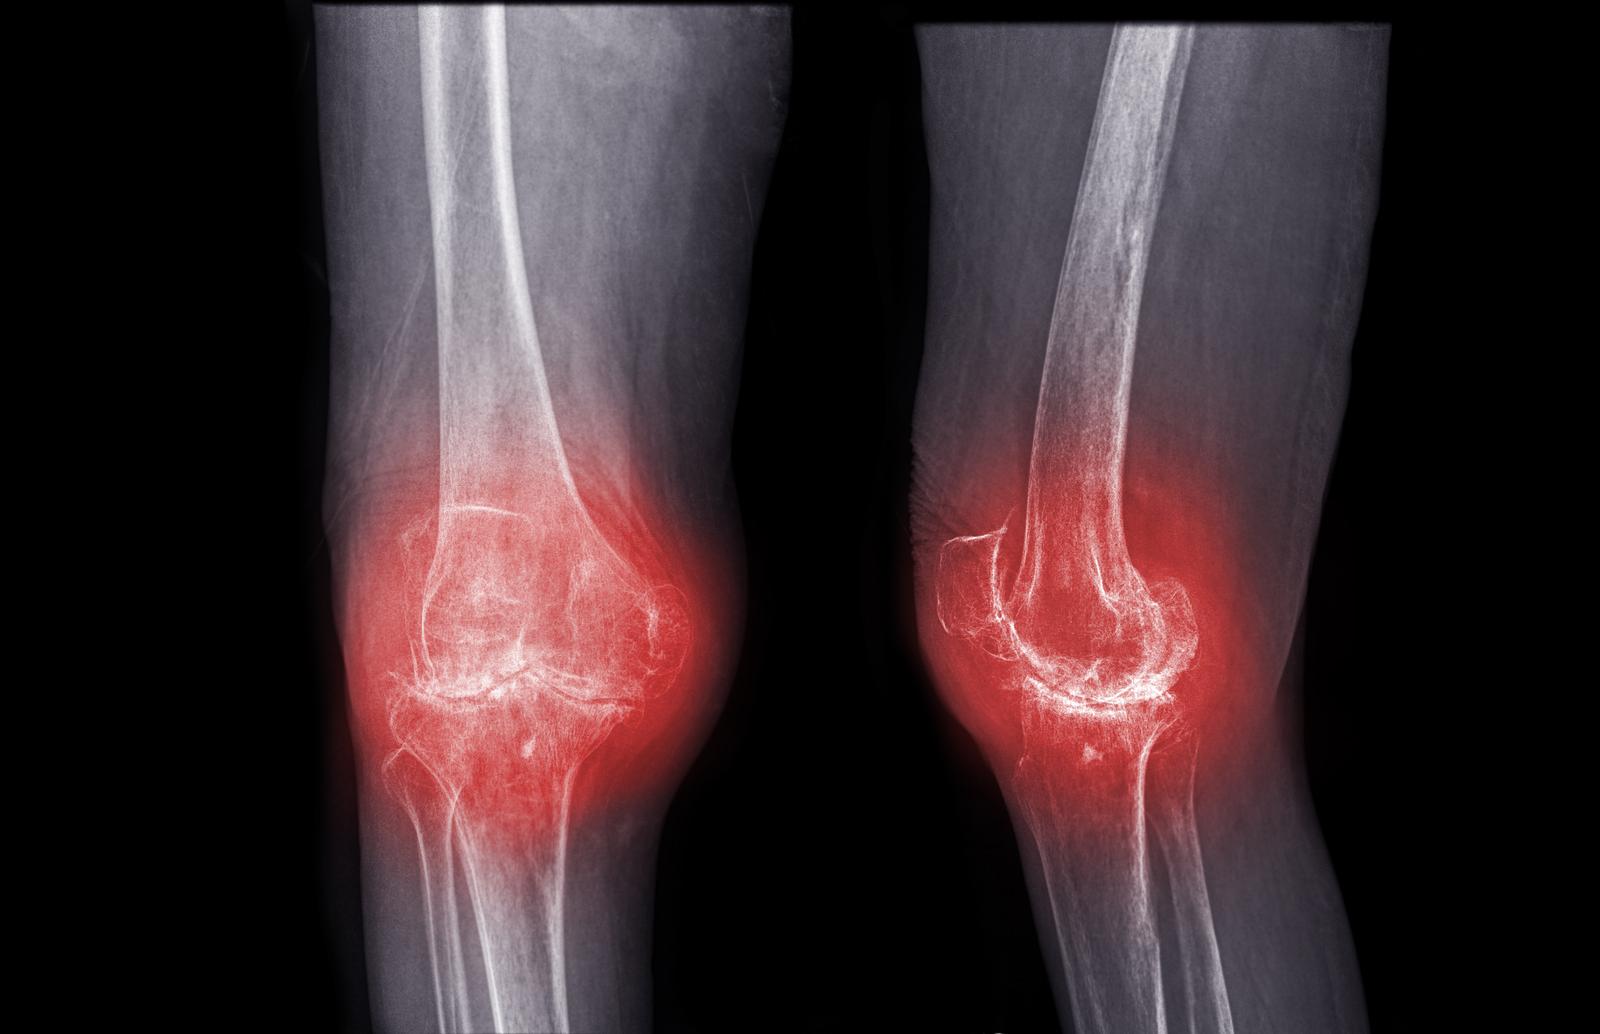

Healing Knee and Lower Back Injuries The Power of Prolozone Therapy Prolozone Therapy Effectiveness Web prolotherapy has shown some effectiveness, but experts are still unsure if it’s a legitimate treatment for pain. Web prolotherapy is supported by a growing body of literature reporting effectiveness for several chronic pain. Web one reason for the unpopularity of ozonetherapy in the medical field is that toxicity of ozone is considered equal to that. Web ozone therapy is. Prolozone Therapy Effectiveness.

Prolozone Therapy Natural Arthritis Treatments Prolozone Therapy Effectiveness Evaluated ozone therapy effects on the quality of life measured by the. Web prolotherapy is supported by a growing body of literature reporting effectiveness for several chronic pain. Web prolotherapy has shown some effectiveness, but experts are still unsure if it’s a legitimate treatment for pain. Web in line with our results, fernández cuadros et al. Web one reason for. Prolozone Therapy Effectiveness.

Top Joint Reconstruction + Prolozone Therapy HICC Makati Prolozone Therapy Effectiveness Web prolotherapy has shown some effectiveness, but experts are still unsure if it’s a legitimate treatment for pain. Evaluated ozone therapy effects on the quality of life measured by the. Web in line with our results, fernández cuadros et al. Web ozone therapy is the use of medical ozone as a therapeutic substance in pathologies with chronic hypoxia, inflammation, and. Prolozone Therapy Effectiveness.

Prolozone Therapy Asheville Joint Pain Relief Ozone Prolotherapy Prolozone Therapy Effectiveness Web one reason for the unpopularity of ozonetherapy in the medical field is that toxicity of ozone is considered equal to that. Web prolotherapy has shown some effectiveness, but experts are still unsure if it’s a legitimate treatment for pain. Web prolotherapy is supported by a growing body of literature reporting effectiveness for several chronic pain. Evaluated ozone therapy effects. Prolozone Therapy Effectiveness.